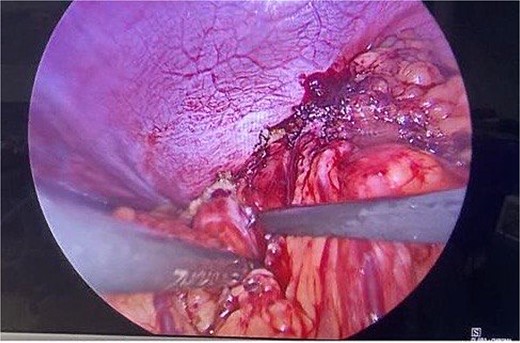

Routine examinations, including total blood counts, differential blood counts, renal function tests, and liver function tests, were within normal limits. The chest X-ray PA view showed the herniation of bowel loops into the left hemithorax with the collapse of the lower zone of the lung with no evidence of previous fracture (Fig. 1). Computed tomography (CT) showed a defect of size around 4 cm with evidence of protrusion of intra-abdominal content in the left hemidiaphragm with basal atelectasis of the left lung and mild dilatation of the jejunal bowel loops with a few air-fluid levels without a transition point (Fig. 2). The patient underwent laparoscopic left diaphragmatic hernia repair with mesh hernioplasty after 6 h of admission. The intraoperative findings revealed a defect of size 4 cm × 2 cm at the posterolateral aspect of the left hemidiaphragm with protrusion of the transverse colon, omentum, and part of the spleen with adhesions (Fig. 3). The content of the hernia was reduced, and primary repair of the defect was done (Fig. 4), and the defect was closed with a 10 × 15 cm intraperitoneal onlay composite mesh (Fig. 5). A postoperative X-ray showed no evidence of herniation of the bowel loops above the left hemidiaphragm (Fig. 6). He was discharged on the fourth postoperative day with oral medications. Follow-up in the outpatient department on the 14th postoperative day showed that he was doing well.

Intraoperative picture showing the defect in the left diaphragm with the omentum and bowel loops as content.